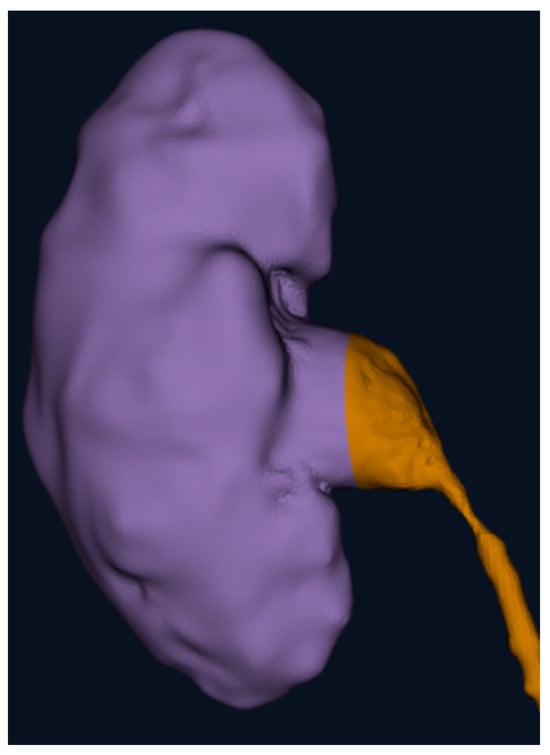

- Patient 2: affected by a splenic cyst of 6 cm, 16 years old, 82 kg, no other comorbidity.